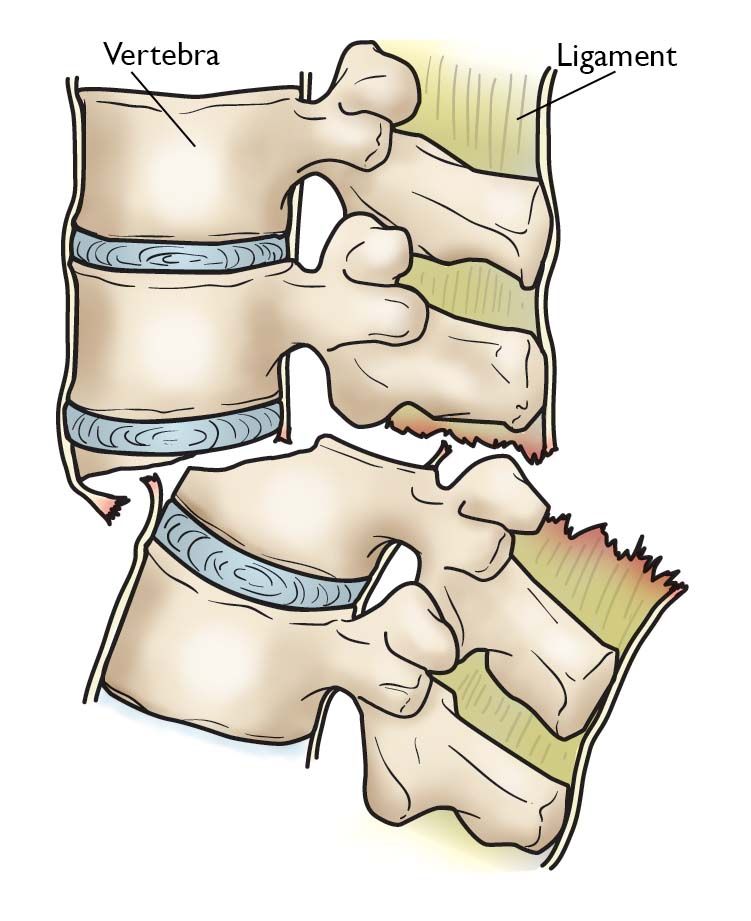

Vertebral facture-dislocation. Fracture-dislocation of the vertebra involves bone and/or soft tissue in which a vertebra moves off an adjacent (nearby) vertebra (displacement).

These injuries:

• Are unstable

• Frequently cause serious spinal cord compression

• Require surgery

Surgical treatment. Fracture-dislocations of the thoracic and lumbar spine are caused by very high-energy trauma. They can be extremely unstable injuries that often result in serious spinal cord or nerve damage. These injuries require surgery to stabilize the spine. The ideal timing of surgery can often be complicated. Surgery is sometimes delayed because of other serious, life-threatening injuries.